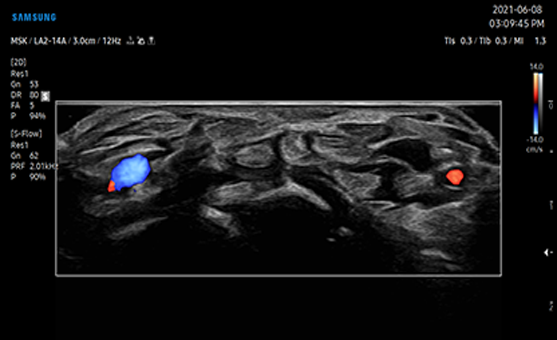

S-Flow , o tehnologie de imagistică Power Doppler direcțională, ajută și la detectarea vaselor de sânge periferice. Vă permite să faceți diagnostice precise atunci când examinarea fluxurilor sanguine este deosebit de complexă.

MV-Flow oferă imagini color avansate pentru vizualizarea structurilor microvasculare cu curgere lentă. Rata de cadre ridicată și filtrarea avansată permit MV-Flow să ofere o vizualizare detaliată a fluxului sanguin spațial.